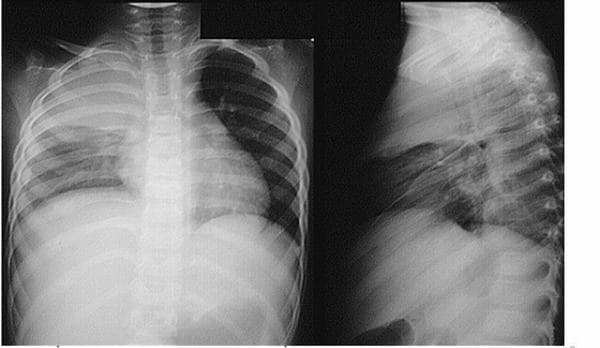

Tràn dịch màng phổi là thuật ngữ dùng để chỉ tình trạng tích tụ dịch trong khoang trống giữa phổi và thành ngực, đó là sự tích đọng dịch có thể là máu, dịch hoặc khí vượt quá mức cho phép của khoang màng phổi. Vậy tràn dịch màng phổi có nguy hiểm không Tràn […]

Tràn dịch màng phổi có thể gặp phải ở mọi lứa tuổi. Vậy tràn dịch màng phổi nguy hiểm không và làm thế nào để điều trị bệnh hiệu quả? Tràn dịch màng phổi là gì? Khoang màng phổi là một khoang ảo nằm giữa phổi và thành ngực. Bình thường nó cũng có một […]

Tràn dịch màng phổi là những bệnh hay gặp trong các bệnh lý về phổi. Bệnh có nhiều nguyên nhân gây ra và xuất hiện những triệu chứng khác nhau. Để hiểu hơn về căn bệnh này bạn có thể tham khảo bài viết dưới đây: Tràn dịch màng phổi là hiện tượng tích tụ […]